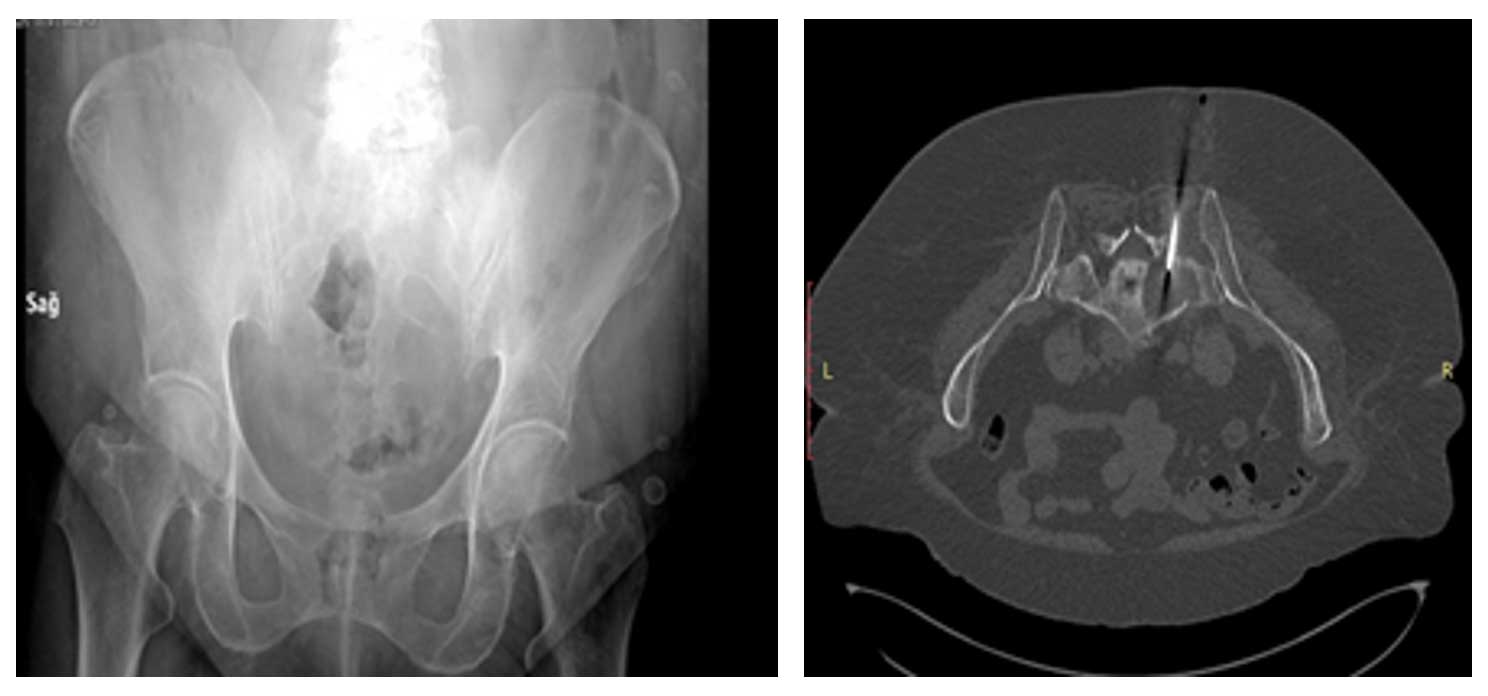

64 yaş kadın hasta, 7 aydır mevcut bel ve sağ kalça ağrısı, sağ bacakta uyuşma ve karıncalanma şikayeti ile başvurmuştur. Tomografi ve iğne biyopsi sonucunda sakrum sağ yarısında kondrosarkom tanısı konmuştur.

Ameliyat Öncesi: Röntgende sakrum sağ tarafta yeniklik, Tomografide tümör içinde iğne biyopsisi görülmekte.